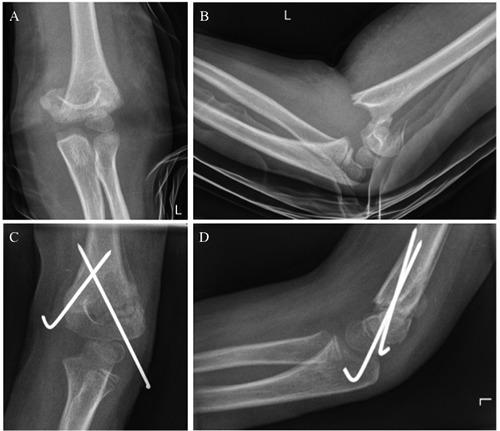

The aim of the study was to identify influencing factors on the complication rate in pediatric supracondylar humerus fractures (PSHF). 22 male and 19 female patients with an extension type PSHF underwent conservative and operative treatment at a single trauma department and were reviewed retrospectively. The complications were assessed and the groups of patients with and without complications were compared according to patient- and therapy-related factors. The overall complication rate was 19.5%. Two patients had a primary and 4 patients a postoperative neurological deficit. One patient developed a pin infection after open reduction and crossed pin fixation. One patient underwent early revision surgery because of insufficient initial reduction after closed reduction and crossed pin fixation. All complications appeared in the surgical treatment group. The appearance of complications was significantly associated with a higher Gartland stage. The median time between trauma and operation was significantly longer in patients without compared to patients with complications. PSHF are associated with a high rate of neurological complications. The Gartland stage and the necessity of surgical treatment are the major influencing factors on the complication rate.

本研究的目的是确定小儿肱骨髁上骨折(PSHF)并发症发生率的影响因素。22例男性和19例女性伸展型PSHF患者在单一创伤科室接受了保守和手术治疗,并进行了回顾性分析。评估并发症情况,并根据患者和治疗相关因素对有并发症和无并发症的患者组进行比较。总体并发症发生率为19.5%。2例患者出现原发性神经功能缺损,4例患者术后出现神经功能缺损。1例患者在切开复位和交叉克氏针固定后发生针道感染。1例患者因闭合复位和交叉克氏针固定后初始复位不充分而接受了早期翻修手术。所有并发症均出现在手术治疗组。并发症的出现与较高的Gartland分期显著相关。与有并发症的患者相比,无并发症患者创伤至手术的中位时间明显更长。PSHF与较高的神经并发症发生率相关。Gartland分期和手术治疗的必要性是并发症发生率的主要影响因素。